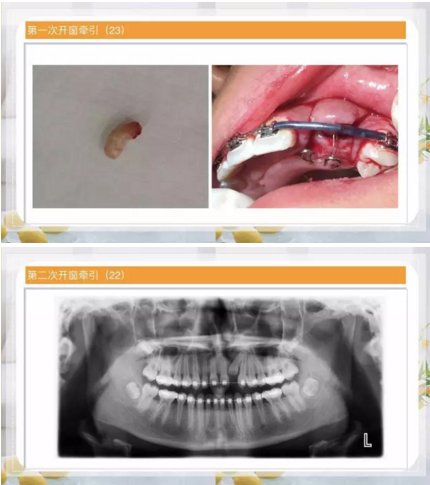

阻生齒外科聯(lián)合正畸治療

24.png

25.png